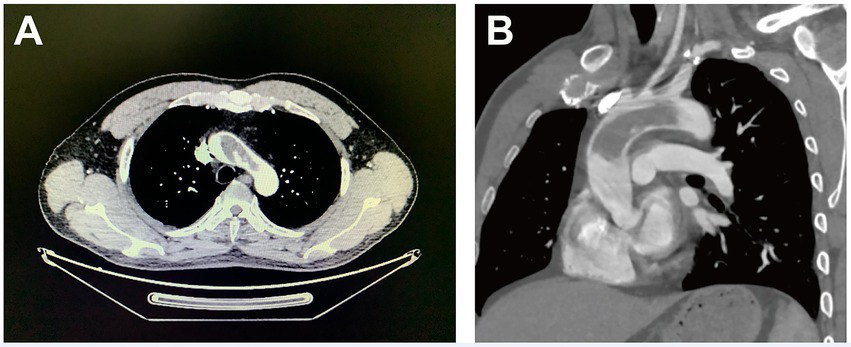

A 43-year-old man with a history of stroke was referred to our department due to a giant mass located in the aorta found incidentally in a local hospital. The patient presented with slurred speech and paralysis of the right limb. No histories of atherosclerosis, coronary artery diseases, hypertension, and trauma were noted. No symptoms of coronary ischemia or thrombosis of the extremities were found. The patient was a non-smoker and was healthy previously with no medications. The contrast-enhanced computer tomography of the whole aorta revealed a low-density lesion without enhancement from the ascending aorta to the arch and ruled out the possibility of malignancy (Figures 1A,B). The results of positron-emission tomography, tumor biomarkers, inflammatory biomarkers, and clotting tests were also normal (Table 1). The biological hemostasis tests, including mutation detection for factor II and factor V, levels of antithrombin III, protein C, protein S, and anti-phospholipid antibodies were within normal ranges. The coronavirus disease 2019 (COVID-19) test was negative. Atrial fibrillation was not detected in the electrocardiogram, and normal cardiac function was found in ultrasonography, without the presence of an intraventricular thrombus, cardiac tumor, patent foramen ovale, and concomitant deep vein thrombosis. Considering the risks for secondary embolic events and myocardial infarction of the floating mass, surgery involving the removal of the aortic mass and thromboendarterectomy was indicated. However, a large infarct area in the left cerebral hemisphere with scattered hemorrhagic lesions was observed on admission by the cerebral computed tomography, and surgery was therefore postponed for 3 weeks (Supplementary Figure S1).

Figure 1. Computer tomography images (cross-section for Panel A and longitudinal-section for Panel B) of a giant floating thrombus from the ascending aorta to the arch.